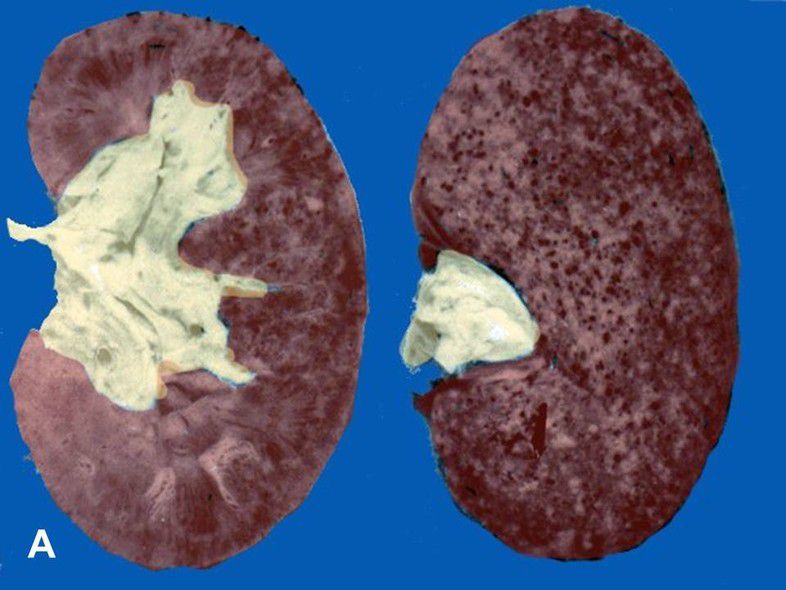

Flea Bitten Appearance of Kidneys

Malignant Hypertension can give rise to a morphologically distinct 'flea bitten' appearance to kidneys. Malignant hypertension causes thrombosis and necrosis in glomeruli. In addition, arterioles undergo fibrinoid necrosis. Reference: https://www.sciencedirect.com/topics/medicine-and-dentistry/malignant-hypertension Image via: https://www.auanet.org/education/auauniversity/education-products-and-resources/pathology-for-urologists/renovascular-diseases/malignant-hypertension